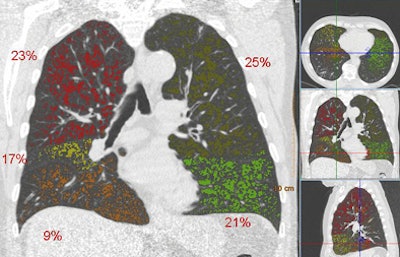

| Above, images from the inspiration scan of a 74-year-old man diagnosed as GOLD stage 3. There is emphysema (dark areas) throughout the lungs, and only the lower right lobe is not substantially affected. Below is the overlay image based on thresholding at -950 HU, including the percentages for each lobe as a whole. Four lobes, except the lower right, are above their cutoff values, meaning that this patient has an emphysema-dominant COPD phenotype. The right lower lobe was also not affected by air trapping. All images courtesy of Bram van Ginneken, MD, PhD. |